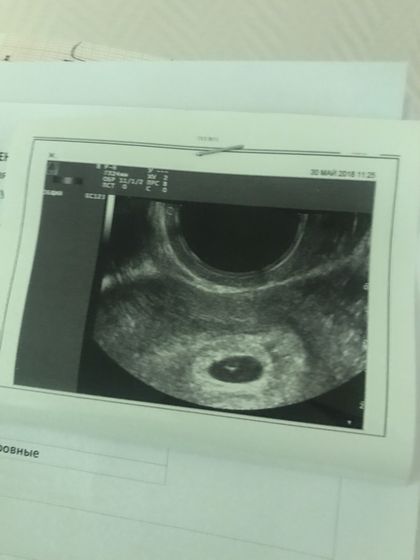

Положили в больничку, после обследования гениколога выделений больше нет, по анализам и УЗИ все хорошо.